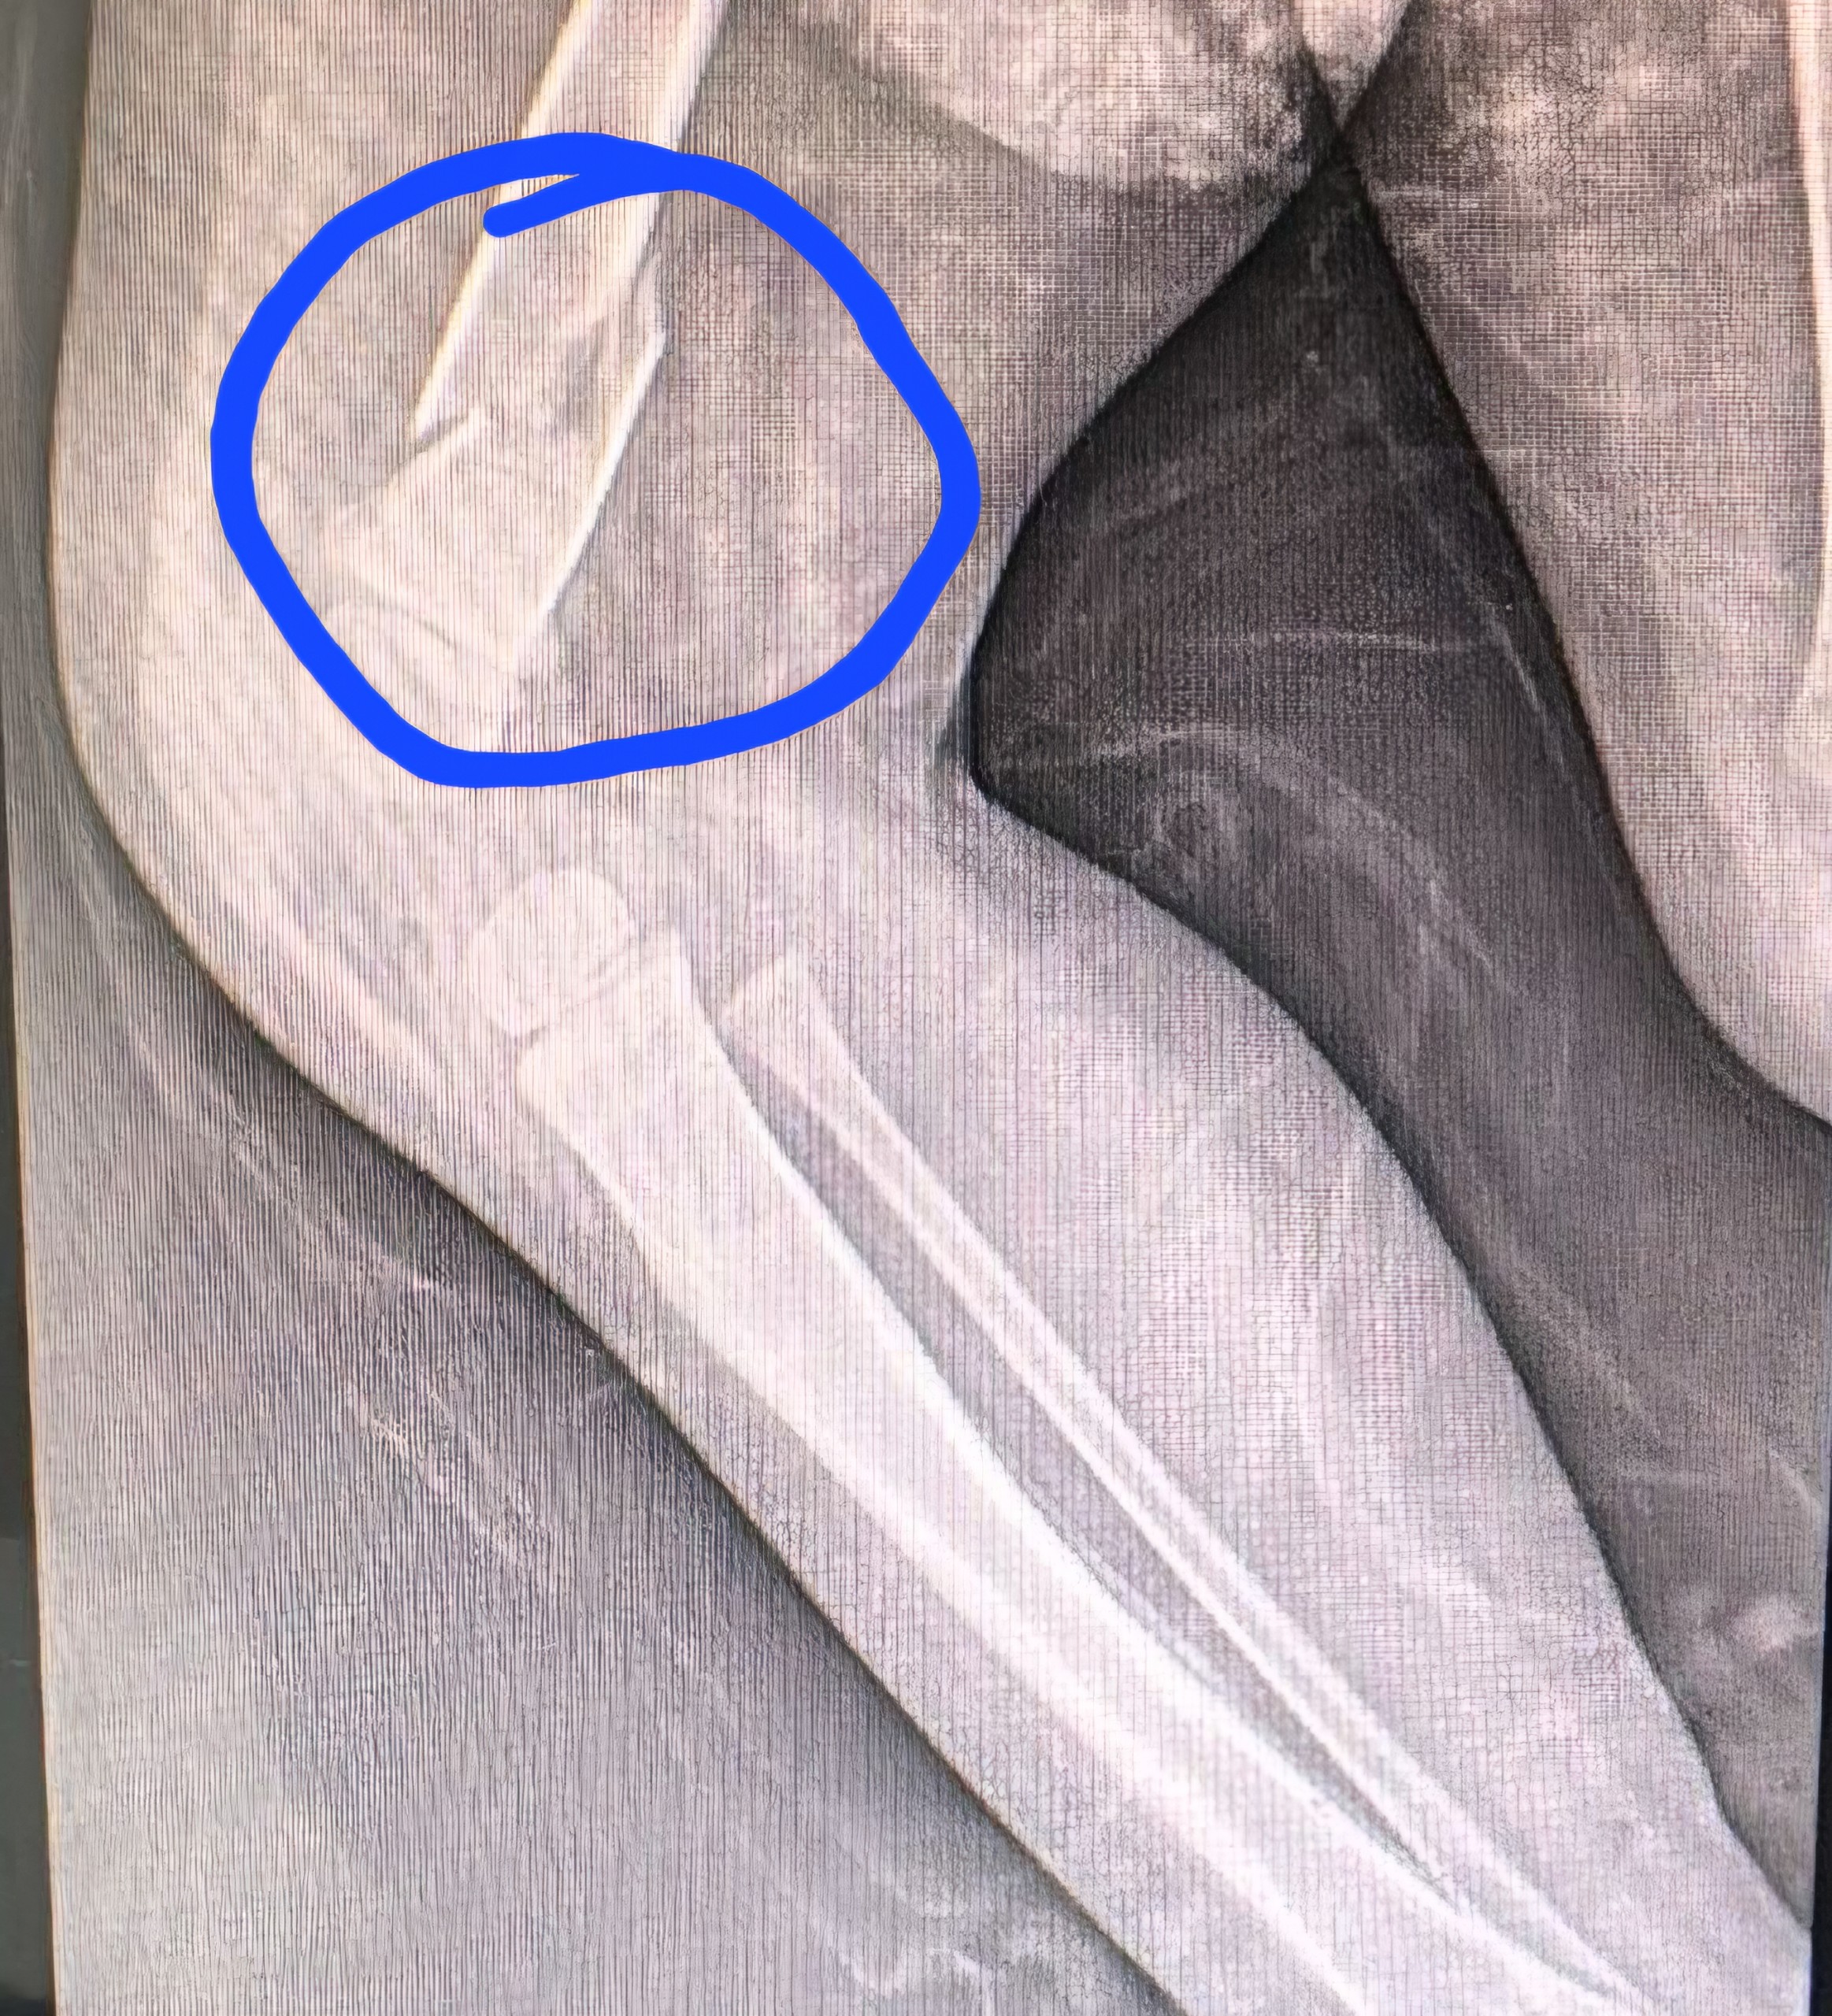

Um bebê de apenas 11 meses deu entrada na emergência do Hospital Santa Catarina, em Criciúma, com múltiplas lesões pelo corpo, incluindo uma fratura no